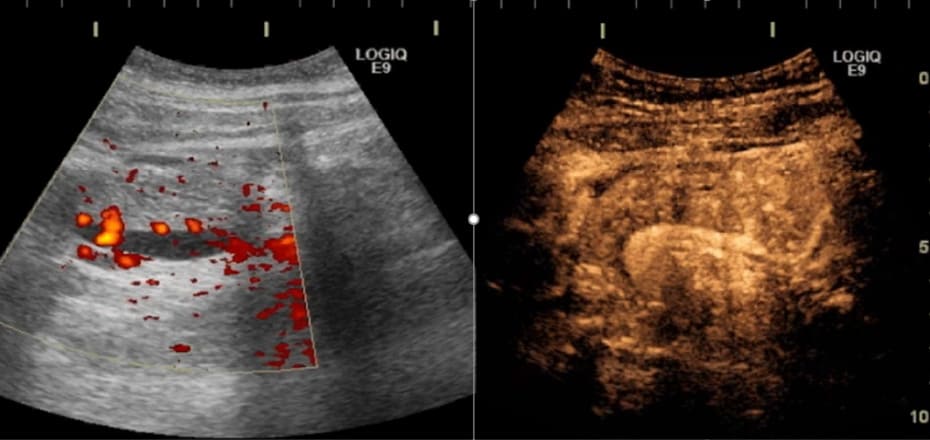

体内の静脈血流を測定することは非常に難しいのですが,当科では造影超音波を使用することで血流の評価を可能としました.

これを用いて静脈血栓症のスクリーニングを行っています.また,移植直後の組織灌流に注目し移植膵機能と相関していることを発見しました.